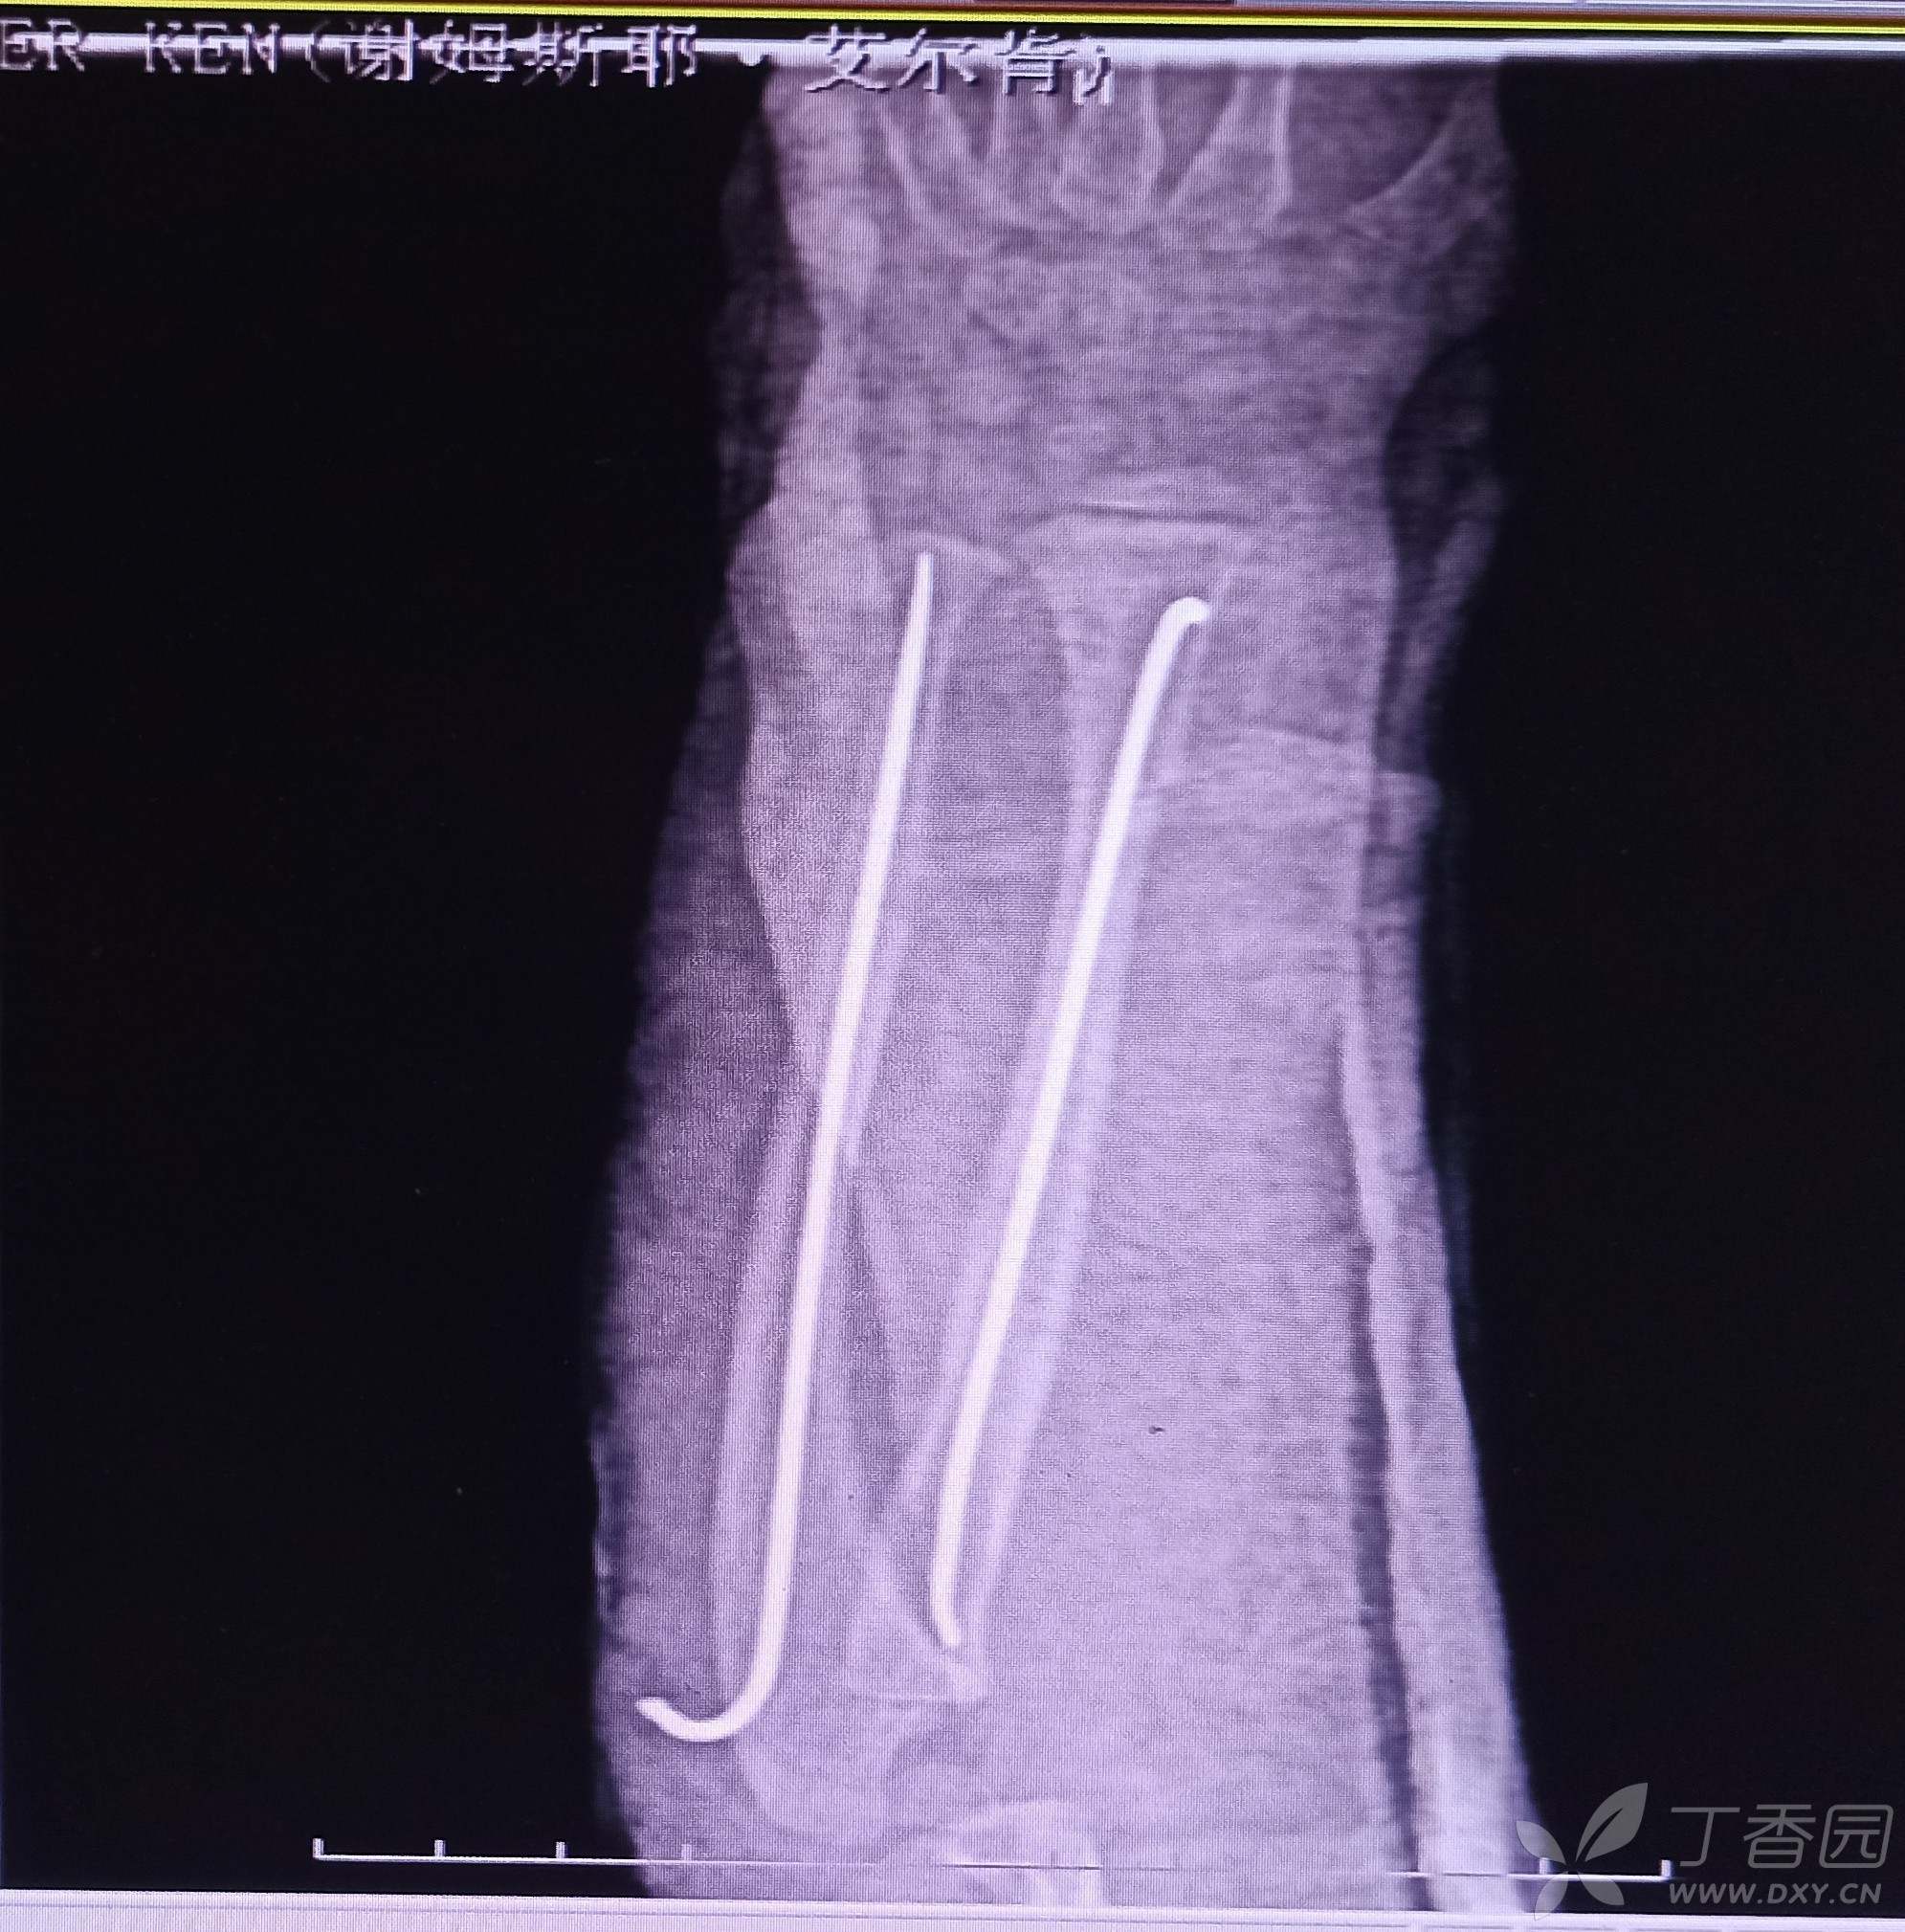

手法牵引复位拍片显示尺骨远端对位对线欠佳,下尺桡关节有分离,给予行弹性髓内钉内固定。遇到这样的各位老师保守还是手术?